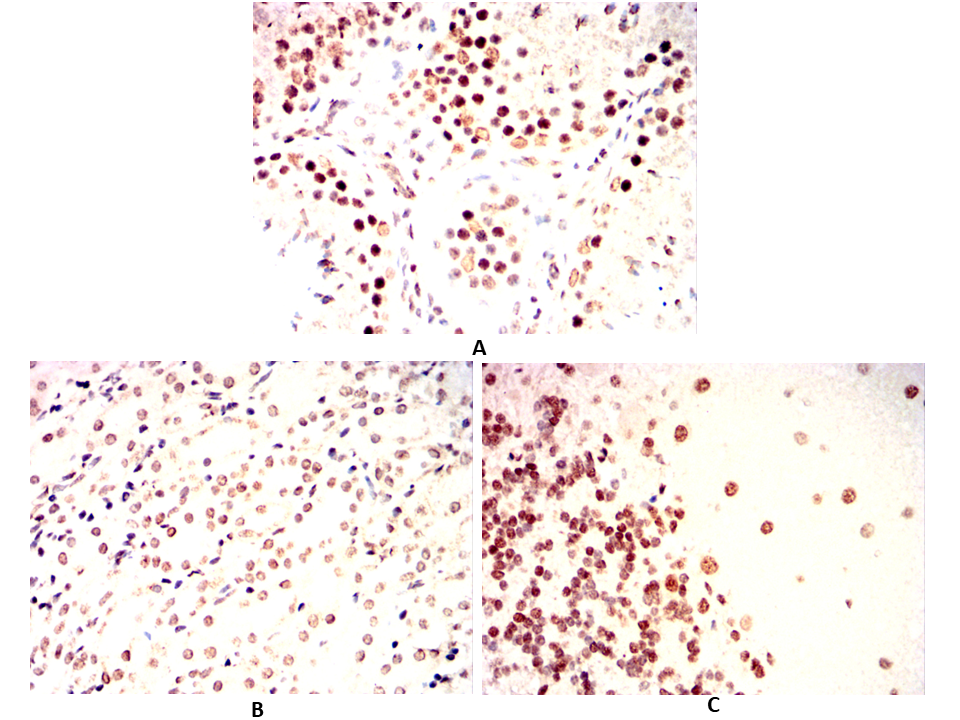

Immunohistochemical analysis of paraffin-embedded Rabbit testicles(A)Rabbit cerebellum(B)Rabbit kidney(C) using EBF1 mouse mAb with DAB staining.